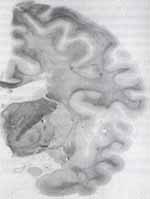

Ya a nivel histopatológico los hallazgos descritos en la literatura, al examinar la sustancia blanca, revelan una proporcionada pérdida de los axones y de las vainas de mielina, que orientan más hacia hipomielinización que desmielinización, aumento del número de oligodendrocitos, disminución de astrocitos y formaciones quísticas como las más características.3

Figura 2: Secciones de la sustancia blanca muestran (A) cambios espongiformes e incremento en el número de núcleos de los oligodendrocitos, (B) además, rarefacción en el centro de la sustancia blanca (C) y cambios microquísticos.3

Figura 3: Sección coronal del hemisferio cerebral izquierdo que muestra la rarefacción de la sustancia blanca con cambios microquísticos.3